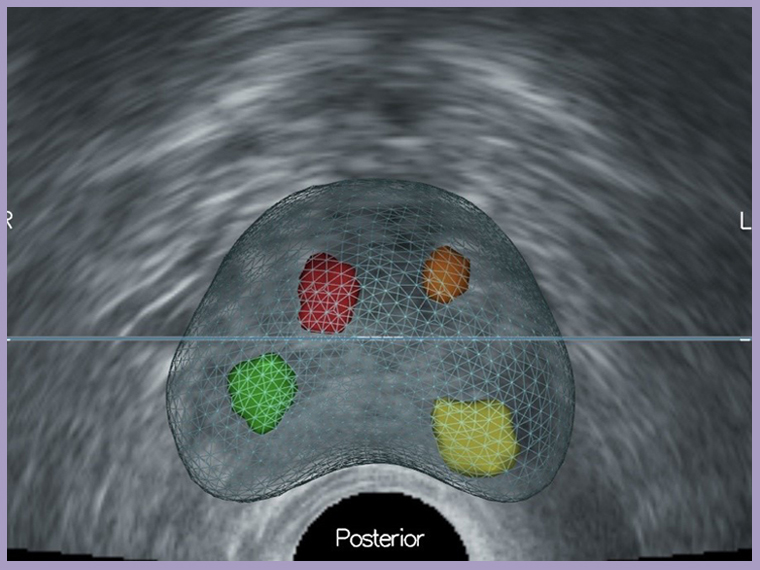

▲經軟體輔助的影像融合能將疑似腫瘤即時呈現在超音波畫面,精準導引切片。(圖/台北慈濟醫院提供)

傳統經直腸隨機切片方式猶如「盲抽」,可能誤判為良性或需重複切片。MRI雖能判讀可疑病灶,卻難以即時定位;超音波則無法準確辨認病灶,因此最適切的診斷方式是將2種影像融合後,進行導引切片。台北慈濟醫院泌尿科團隊導入軟體輔助影像融合切片技術,先由MRI標記病灶,再於即時超音波中進行影像疊合與校準,鎖定病灶進行經會陰切片,大幅提升精準度,並因避開直腸入針,大幅降低感染與敗血症風險,惟檢查時需全身麻醉。

鐘伯恩醫師與台北慈濟醫院泌尿科團隊,將此種檢查方式的臨床研究成果發表於國際泌尿科醫學期刊《The Journal of Urology》與《Urological Science》,研究顯示,影像融合誤差超過5%時,容易導致低估病灶分期,而使用「軟體輔助」影像融合攝護腺切片,可於目標區域增加約20%的癌症診斷率。與傳統經直腸切片的技術相比較,能更有效提高切片精準度。